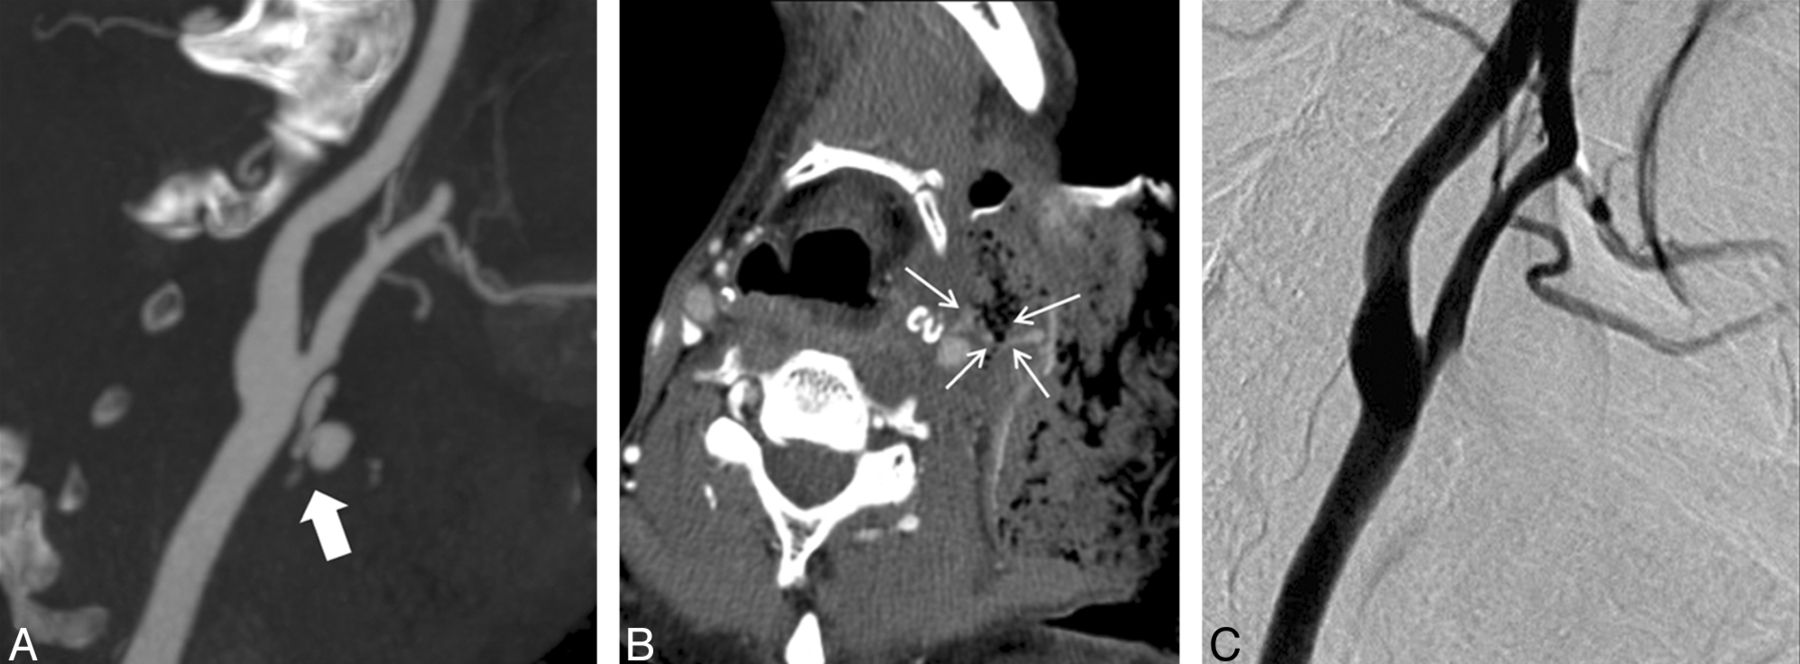

A 52-year-old man with a history of oropharyngeal cancer. A, MIP CTA imaging performed after bleeding was controlled by local packing shows contrast extravasation (arrow) from the common carotid artery near the bifurcation. B, Source image shows an exposed common carotid artery (arrows) surrounded by necrosis. C, DSA done immediately after CTA does not show contrast extravasation. However, the possibility of a further tamponade effect after CTA cannot be excluded in this case.